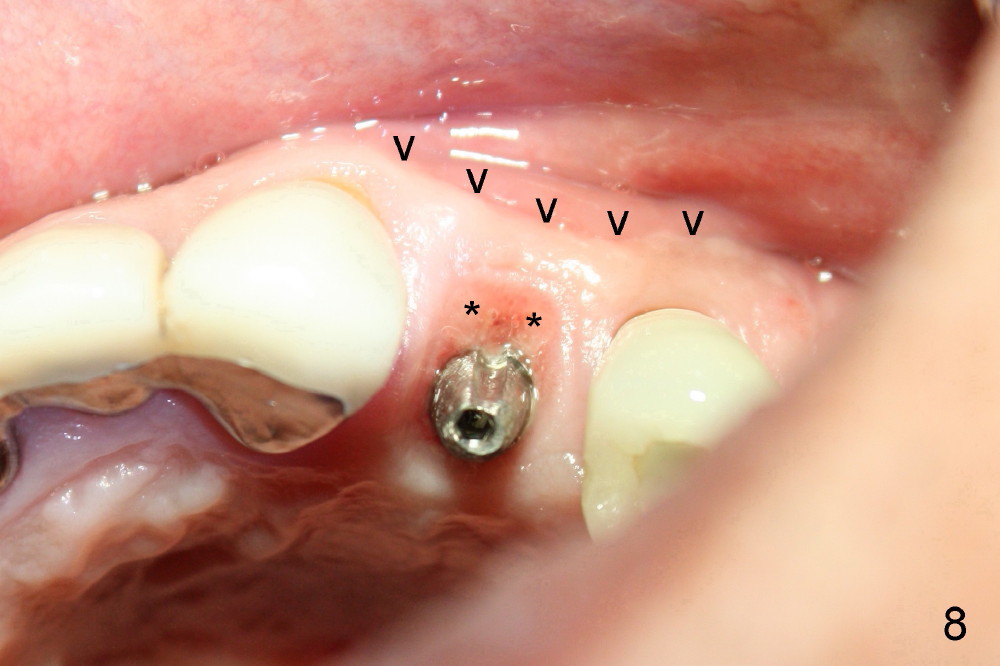

A 50-year-old man has mild pain in the upper left 1st bicuspid 3 years after root canal retreatment with placement of two posts (Fig.1). Findings of clinical exam are consistent with root fracture (Fig.2). Extraction reveals two fused roots (Fig.3,4). Probing indicates that the buccal plate is defective. Osteotomy is initiated in the palatal socket with a 2 mm pilot drill, followed by 2.5 and 3.0 mm reamers and 4.5x20 mm tap. The septum appears to have been pushed buccally (Fig.5 *) and form a new buccal wall (partially, strengthened by bone graft mentioned below) for the implant to be placed. The implant (4.5x20 mm) is placed in the palatal socket (Fig.6 *) with insertion of an abutment (A: 3.5x5 mm 0º), while a mixture of autogenous bone (harvested from reamers) and Synthograft (Bicon) is placed in the shrunken buccal socket (Fig.7; using allograft may decrease postop bony shrinkage). The bone graft is then contained by an immediate provisonal without collagen membrane or flaps. The patient is doing well postop. The gingiva is healthy (Fig.8*) when the provisional is removed 3 months postop with normal papillae (Fig.9 arrowheads). It remains the same 1 month post cementation (Fig.10,11). For further follow up, see immediate implant of the tooth #13.